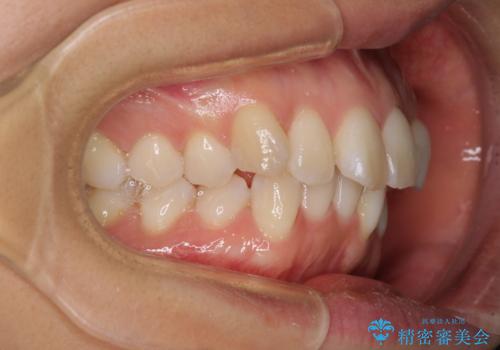

前歯のデコボコを抜歯矯正で改善 メタル装置で費用を抑える

- 前歯のデコボコと口元の突出感を気にして来院された患者様です。

非抜歯矯正ではデコボコを解消することでより口元が突出してしまうため、上下左右の小臼歯4本の抜歯を行い、ワイヤー装置による矯正治療を行うこととしました。

もう少し口元の突出感を改善したかったのですが、舌の突出癖が影響し下顎前歯が唇側に押させる仕上がりとなりました。